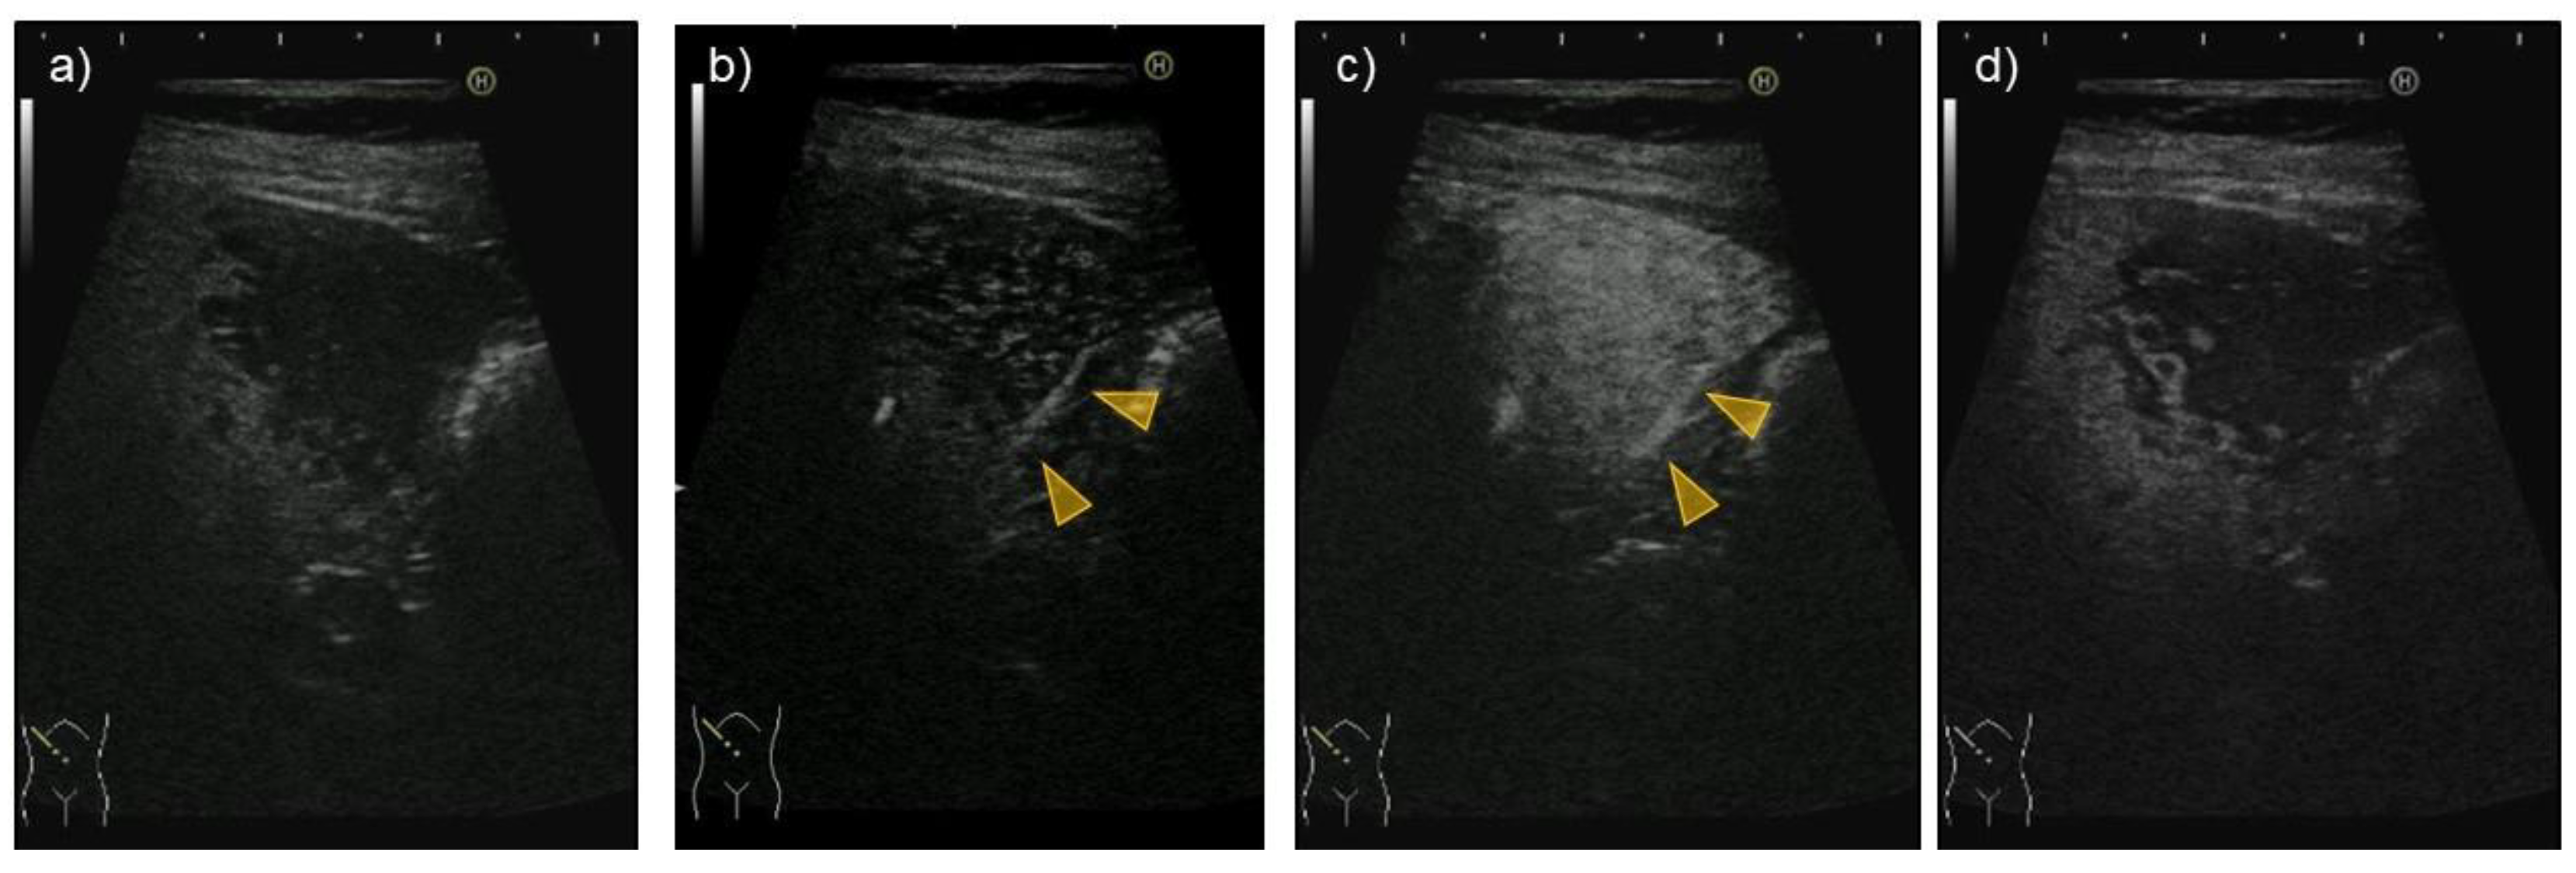

| US | Hypoechoic | Hypoechoic | Presence of halo and mosaic signs |

| CEUS | Arterial phase: hyper-enhanced Portal/late phase: hypo-enhanced | Arterial phase: hyper-enhanced Portal/late phase: hypo-enhanced | Arterial phase: hyper-enhanced Portal/late phase: hypo-enhanced |